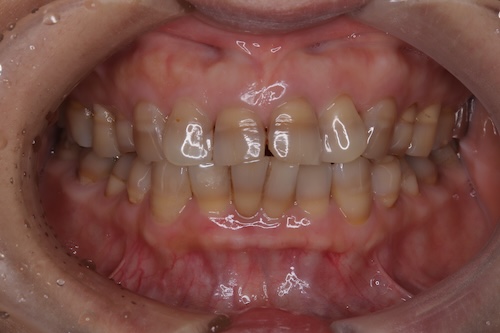

テトラサイクリン歯による着色が見られる40代の女性

- 施術後

テトラサイクリン症例のため、あらかじめ、色の差は残ることや、真っ白にはならないことをお伝えし、完成のイメージに大きな差がないように、初診カウンセリング時に時間をかけて症例を用いてご説明することを心がけました。